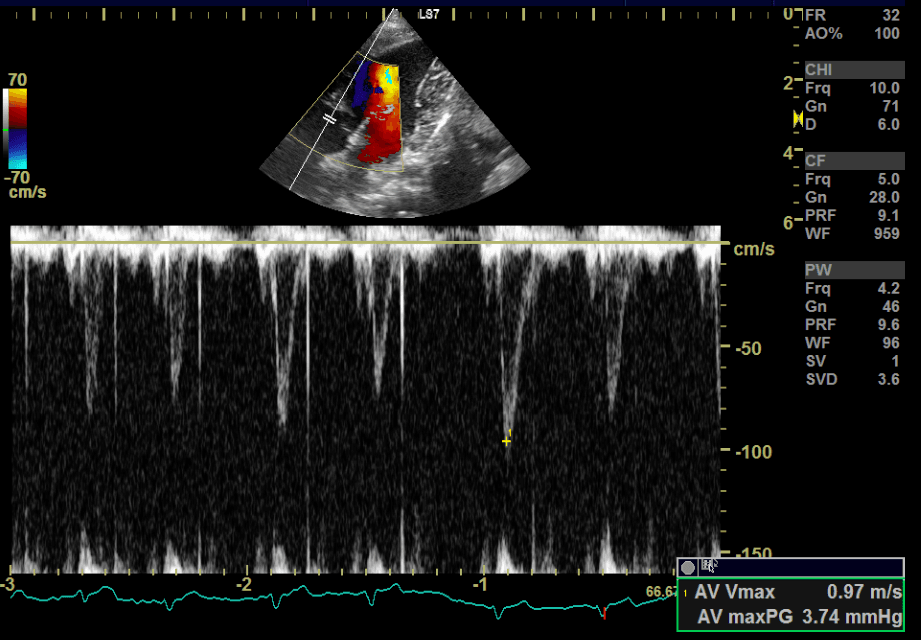

初期段階では症状がほとんど出ないため、聴診での心雑音のチェックが最初の入り口となります。聴診で心臓の雑音が確認された場合は、レントゲン検査、心臓超音波(エコー)検査、心電図、血圧測定などを行い、心臓の拡大や逆流の程度を正確に評価します。

↑色々な数値を測定して総合的に診断し、治療計画を立てます。